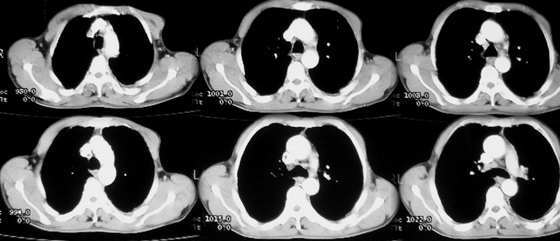

以下是引用jiajie在2005-11-6 22:07:00的发言:[br]1)左肺下叶阻塞性肺炎,胸腔积液,中心型肺癌可能大,建议纤支镜。[br]2)结合30年打石史,双肺弥漫性小结节考虑矽肺。

以下是引用sdqzwyx在2005-11-7 19:59:00的发言:[br]双肺弥漫大小不等的粟粒状结节影;肺纹理走行失去自然,粗细不均,边缘不规则,小叶间隔增厚;左上肺示不规则形致密影,从斑块边缘向周围伸出长短不一的致密索条影,临近的血管、支气管和叶间胸膜等结构受牵拉移位;左下肺示不规则团块状影,其内示空洞,洞内壁尚光整,左侧胸腔积液。右肺下叶背段亦示部分病灶融合。双肺可见局限性肺气肿。[br]诊断:结合病史符合三期矽肺表现(少数矽肺纤维斑块内可以形成空洞,一般认为是斑块中央感染引起坏死所致)但尘肺病人易合并肺结核,诊断可为三期+tb。所以此病人应进一步检查是否合并结核。